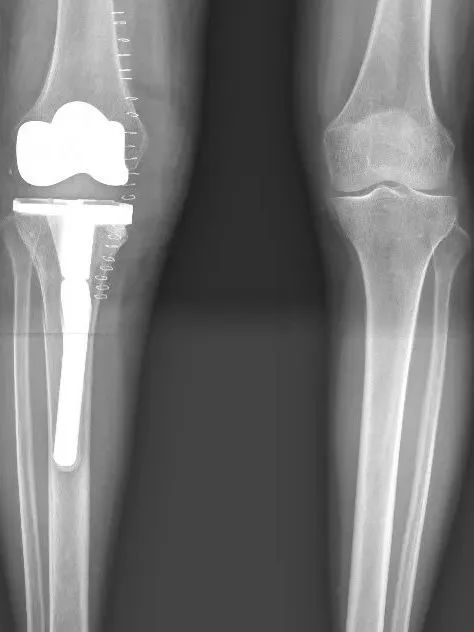

“难道我再也无法站起来走路了吗?往后该怎么办?”在杭州市红十字会医院骨科诊室,确诊为膝关节结核的鲍女士一度陷入绝望。

医生告诉她,干骺端骨质严重破坏,关节稳定性丧失,已发展为安德森Ⅱa型骨缺损。传统抗结核药物、常规清创术及常规关节置换手术难以恢复关节功能,日常生活将会受到极大影响。

“别轻易放弃,我们与你一起渡过难关!”骨科沈健主任医师团队仔细研究鲍女士的情况后,决定为其实施全膝关节置换术。

据主刀医生沈健主任医师介绍,膝关节结核的全关节置换术技术难度大,既要彻底清除结核病灶防止死灰复燃,又要在被严重破坏的骨质结构中重建稳定的关节系统,难度堪比“在废墟上重建宫殿”。

该院骨科、麻醉科、康复科等多学科团队精准协作,制定了个性化综合治疗方案。术后2天鲍女士便实现了床边站立,术后3天借助助行器可自主行走。出院时她激动地向骨科医护团队道谢:“感谢你们!让我的生活回归正常!”